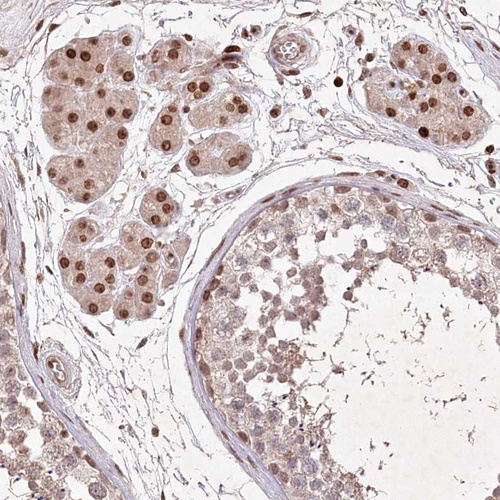

Immunohistochemical staining of human testis shows strong nuclear positivity in Leydig cells.